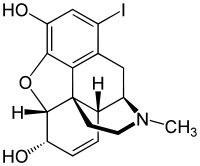

Halogenated morphine derivatives

- 1-Bromocodeine

- 1-Chlorocodeine

- 1-Iodomorphine

Structures

| Other open chain opioids | ||||

|---|---|---|---|---|

1-Bromocodeine |

1-Chlorocodeine |

| ||